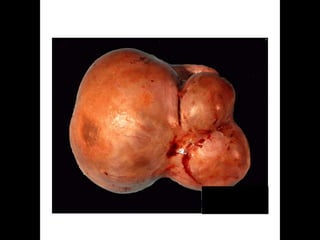

1. MUCINOUS CYST ADENOMA

MUCINOUS CYST ADENOMA.

 ORIGIN:-

 It arises from the totipotent surface epithelium of the

ovary.

 It arises from the teratoma in which, the epithelium of

epidermal origin have probably overgrown than the

other elements.

 QUITE COMMON : 20-25% OF ALL OVARIAN

TUMOURS…

 USUALLY BILATERAL IN 10% CASES

 MALIGNANCY CHANCES : 5-10%

 NAKED EYE APPEARANCE

 MAYATTAIN HUGE SIZE IF LEFT UNCARED

FOR…

 WALL IS SMOOTH, LOBULATED WITH WHITISH

OR BLUISH WHITE HUE..

 AT PLACES, IT IS THIN SO AS TO BE

TRANSLUCENT…